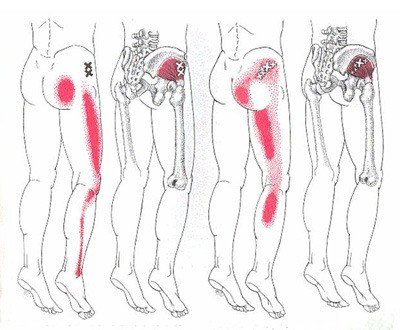

그런데 근육 중에서도 특히 엉덩이 주변의 근육이 뭉치게 되면 근육손상 부위의 주변부로 통증이 퍼져나가는 특징이 있는데, 이런 통증은 디스크 탈출증과 감별을 해서 치료해야합니다. 이런 통증을 디스크라고 불러서는 안될 것입니다. 그리고 근육에 대한 압통점검사나 통증유발검사, 그리고 신경학적 검사를 통해서 구분을 해나가야 하겠지요. 몇가지 근육을 더 보겠습니다.

이상근, 소둔근의 통증유발점입니다. 디스크로 오해할 수도 있겠지요?

그런데 근육에 의한 통증이 왜 말초의 통증으로 인지될까요? 통증유발점에 의한 통각이 척수 후각으로 들어가는 과정에서 이 주변부에서 오는 감각신경고 섞이면서 혼선이 오기 쉽기 때문입니다. 그래서 이 통증이 근육에서 온 통증이지만 다른 부위가 아픈 것처럼 느낄 수 있습니다. 그러나 이 통증은 디스크에 의한 통증이 아닙니다. 근육에 의한 통증으로 근막통증증후군이라는 다른 병명이 있기 때문입니다.